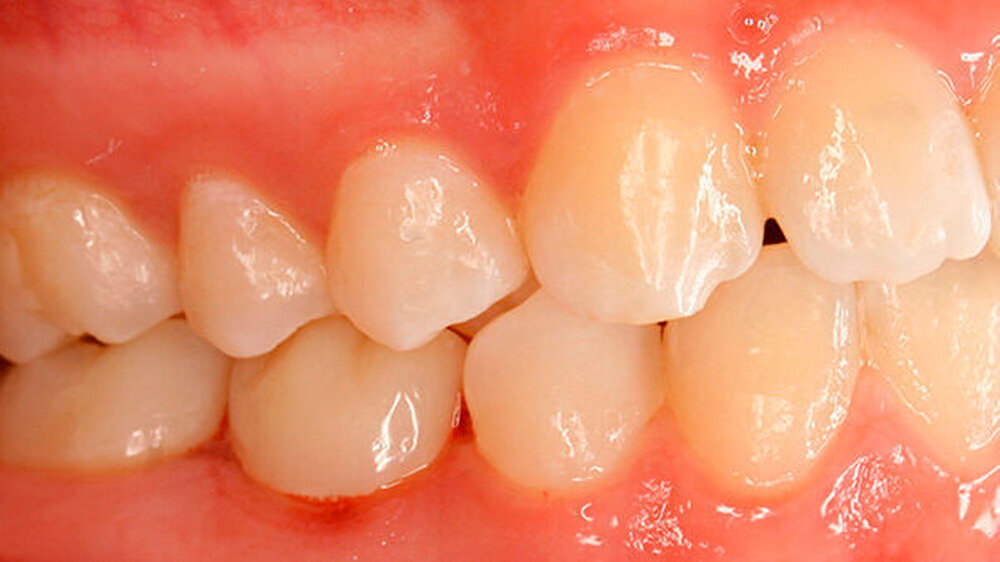

Die Patientin zeigte ein kariesfreies bleibendes Gebiss mit Nichtanlage des Zahns 35 und Persistenz des Zahns 75 auf (Abbildung 1). Sie wies im Frontzahnbereich sowie im rechten Seitenzahnbereich eine Klasse I auf, im linken Seitenzahnbereich aufgrund der Größe des Zahns 75 eine Klasse II. Zahn 75 befand sich in deutlicher Infraokklusion (Abbildung 2). Der Perkussionstest wies allerdings nicht eindeutig auf eine Ankylosierung hin.